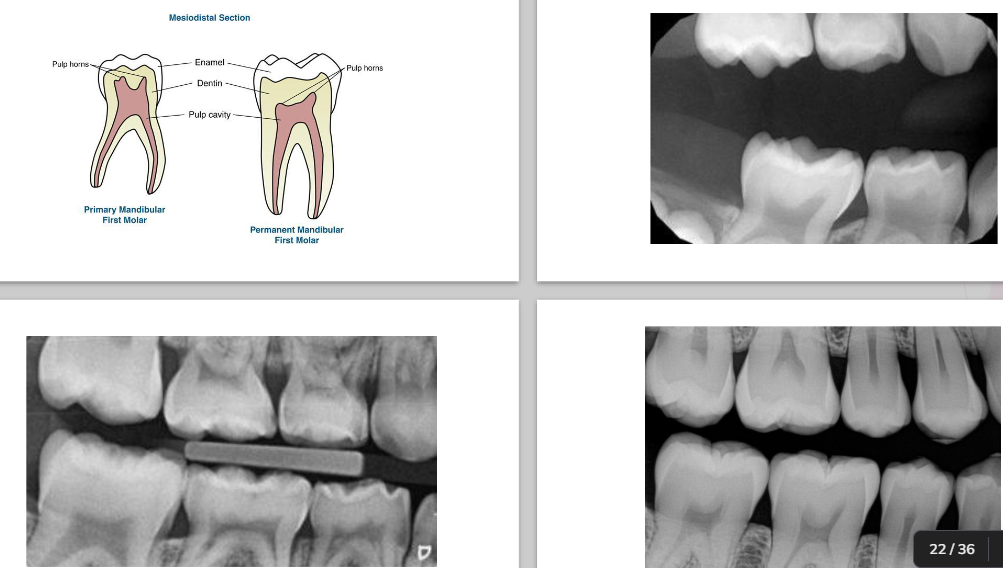

Morphological differences

Primary:

• shorter

• narrow occlusal table

• constricted in the cervical portion

Permanent:

• bigger

• broad occlusal table

• cervical constriction is not well marked

<p><strong><u>Primary:</u></strong></p><ul><li><p>shorter</p></li><li><p>narrow occlusal table</p></li><li><p>constricted in the cervical portion&nbsp;</p></li></ul><p><strong><u>Permanent:</u></strong></p><ul><li><p>bigger</p></li><li><p>broad occlusal table</p></li><li><p>cervical constriction is not well marked&nbsp;</p></li></ul><p></p>

Primary characteristics

 Thinner enamel and dentin layers

 Enamel rods in the cervical area directed occlusally

 Broad flat contacts

 Color is usually lighter

 Mesio-buccal cervical bulge seen in primary molars

 Incisors have no developmental grooves

• Mamelons

<p><span><strong> Thinner enamel and dentin layers </strong></span></p><p><span><strong> Enamel rods in the cervical area directed occlusally </strong></span></p><p><span><strong> Broad flat contacts </strong></span></p><p><span><strong> Color is usually lighter</strong></span></p><p><span><strong> Mesio-buccal cervical bulge seen in primary molars </strong></span></p><p><span><strong> Incisors have no developmental grooves </strong></span></p><ul><li><p><span><strong>Mamelons  </strong></span></p></li></ul><p></p>

Permanent Characteristics

 Thick enamel and dentin

 Enamel rods in the cervical are directed gingivally

 Point contacts

 Color is much darker (not as white)

 Have mamelons

 Less prominent cervical bulge in molars

<p><span><strong> Thick enamel and dentin </strong></span></p><p><span><strong> Enamel rods in the cervical are directed gingivally </strong></span></p><p><span><strong> Point contacts </strong></span></p><p><span><strong> Color is much darker (not as white)</strong></span></p><p><span><strong> Have mamelons </strong></span></p><p><span><strong> Less prominent cervical bulge in molars </strong></span></p>